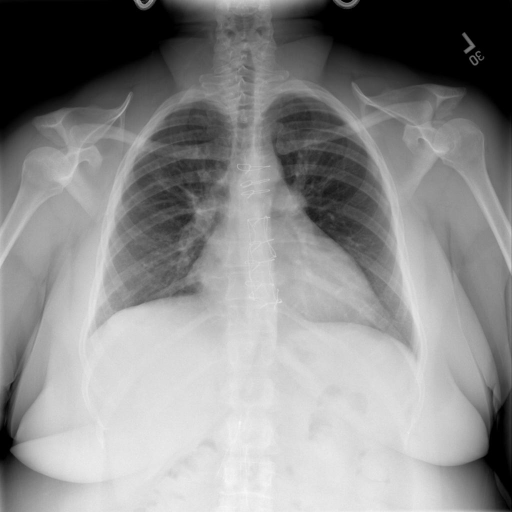

- (1)准备[诊疗报告(中文)](./data/Xray/openi-zh.json)和[X光影像](https://pan.baidu.com/s/13GBsDMKf6xBZBSHpoWH_EA?pwd=k9sh)在`data/Xray`文件夹下; - (2)开始训练: ```bash # 设置CUDA变量,主要是为了解决有时候直接训练而出现无法正确加载到显卡问题 export CUDA_VISIBLE_DEVICES=0,1,2,3 # 开始训练 bash finetune_XrayGLM.sh ``` 这里的复现过程非常简单,主要是很多过程我们都为大家准备好了,大家可以随时复现一个自己的`XrayGLM`。 ### 4.模型训练(通用) - [【官方视频教程】XrayGLM微调实践](https://www.bilibili.com/video/BV1Yh4y147gx/) - [复旦大学《大语言模型理论与实践》](https://intro-llm.github.io/) ## 效果展示 *以下效果来自于**低质量**的数据训练和权重 影像诊断: |X光影像|诊疗报告(医生)|XrayGLM| |:-|:-|:-| |![](./data/Xray/2_1.png)|根据X射线图像,心脏大小正常,肺部看起来很清晰。已经排除了肺炎、积液、水肿、气胸、腺病、结节或肿块的存在。该发现表明一切正常。换句话说,总体印象是胸部正常。|X光片显示,心脏大小正常。肺部没有气胸或胸腔积液的证据。骨骼结构看起来没有任何异常。总的来说,X光片表明没有发现急性心肺疾病的迹象。| |![](./data/Xray/2882_1.png)|X光图片显示没有扭曲的区域、可疑的骨质不透明度或胸腺积液。心脏大小轻微增大,但非常稳定。此外,没有气胸的证据,肺野也正常。总体来说,X光片显示没有急性心脏异常,但要注意轻微的心脏扩大。|X光片显示,心脏大小正常。肺部和纵隔轮廓清晰,没有气胸或胸腔积液的证据。骨骼结构完整,没有任何急性异常。| |![](./data/Xray/2577_1.png)|心影形态在正常范围内。没有急性骨质异常。有可能出现没有明显的吸水或肺实质状况的线索。没有大面积积液或气胸。有可能怀疑其有误吸或肺实质问题。为了确诊和治疗,可能需要进行适当的影像学随访。|心脏大小正常,肺部和纵隔轮廓清晰。没有急性异常或活动受限的证据。没有任何明显的气胸、胸腔积液或肺不张的迹象。此外,也没有发现任何局灶性骨质异常或其他急性疾病。| 多轮对话: |X光影像|诊疗报告(医生)| |:-|:-| |![](./data/Xray/861_1.png)|右侧主动脉突出观察到。心脏大小正常。胸部未发现明显的肺气肿、胸膜积液或可疑的肺部病变。报告指出已知右侧主动脉情况正常。| ```bash >> X光影像路径:./data/Xray/861_1.png >> 用户:这是一张什么图? >> XrayGLM:这张图片显示的是一张肺部检查的X光片。 >> 用户:请描述这张胸部X光片的诊断结果 >> XrayGLM:心脏大小正常,肺部清晰。没有急性心肺疾病的证据。 >> 用户:是否存在肺气肿? >> XrayGLM:没有肺气肿。心脏大小正常,肺部清晰。没有发现急性心肺疾病的证据。 >> 用户:平时饮食该注意什么? >> XrayGLM:饮食应该健康,均衡。建议增加蛋白质的摄入量,因为蛋白质有助于维持肌肉和骨骼的健康。多食用蔬菜、水果、全谷物以及健康的脂肪来源如橄榄油、鱼类等可以帮助获得足够的维生素和矿物质。此外,避免过度饮酒或吸烟,这些习惯可能会对心脏健康产生负面影响。 ``` ## 未来展望 1. 模型的能力更多来源于数据的支持,`OpenI-zh`作为微调数据集,其数据量足以支持研究,在更广泛的任务和性能表现上,我们认为**在大规模数据集上预训练并在高质量少量数据集上微调是一种可行的方案**; 2. 普遍意义的理解上,视觉多模态模型=视觉模型+语言模型。除了需要关注视觉模型信息与语言模型输出的搭配外,还需要**额外关注到语言模型的加强,在人机的对话中,尤其是医疗语言模型的问答上,除了专业的医疗问题回答,带有人文情怀的有温度的回答更应该是我们追寻的目标**。 3. **高精度的模型永远打不过大参数的模型**,如果在6B模型和13B模型上选择微调,请在资源充足情况下选择13B的大参数模型; ## 项目致谢 1. [VisualGLM-6B](https://github.com/THUDM/VisualGLM-6B)为我们提供了基础的代码参考和实现; 2. [MiniGPT-4](https://github.com/Vision-CAIR/MiniGPT-4)为我们这个项目提供了研发思路; 3. ChatGPT生成了高质量的中文版X光检查报告以支持XrayGLM训练; 4. [gpt_academic](https://github.com/binary-husky/gpt_academic)为文档翻译提供了多线程加速; 5. [MedCLIP](https://github.com/RyanWangZf/MedCLIP) 、[BLIP2](https://huggingface.co/docs/transformers/main/model_doc/blip-2) 、[XrayGPT](https://github.com/mbzuai-oryx/XrayGPT) 等工作也有重大的参考意义; ![](./assets/images/mpu.png) 这项工作由[澳门理工大学应用科学学院](https://www.mpu.edu.mo/esca/zh/index.php)硕士生[王荣胜](https://github.com/WangRongsheng) 、[段耀菲](https://github.com/IsBaSO4) 、[李俊蓉](https://github.com/lijunrong0815)完成,指导老师为檀韬副教授、[彭祥佑](http://www.patrickpang.net/)老师。 *特别鸣谢:[USTC-PhD Yongle Luo](https://github.com/kaixindelele) 提供了有3000美金的OpenAI账号,帮助我们完成大量的X光报告翻译工作 ## 免责声明 本项目相关资源仅供学术研究之用,严禁用于商业用途。使用涉及第三方代码的部分时,请严格遵循相应的开源协议。模型生成的内容受模型计算、随机性和量化精度损失等因素影响,本项目无法对其准确性作出保证。即使本项目模型输出符合医学事实,也不能被用作实际医学诊断的依据。对于模型输出的任何内容,本项目不承担任何法律责任,亦不对因使用相关资源和输出结果而可能产生的任何损失承担责任。 ## 项目引用 如果你使用了本项目的模型,数据或者代码,请声明引用: ```bash @misc{wang2023XrayGLM, title={XrayGLM: The first Chinese Medical Multimodal Model that Chest Radiographs Summarization}, author={Rongsheng Wang, Yaofei Duan, Junrong Li, Patrick Pang and Tao Tan}, year={2023}, publisher = {GitHub}, journal = {GitHub repository}, howpublished = {\url{https://github.com/WangRongsheng/XrayGLM}}, } ``` 我们的工作被[Evaluating Large Language Models for Radiology Natural Language Processing](https://arxiv.org/abs/2307.13693)引用,希望大家去关注一下相关的工作! ## 使用许可 此存储库遵循[CC BY-NC-SA](https://creativecommons.org/licenses/by-nc-sa/4.0/) ,请参阅许可条款。